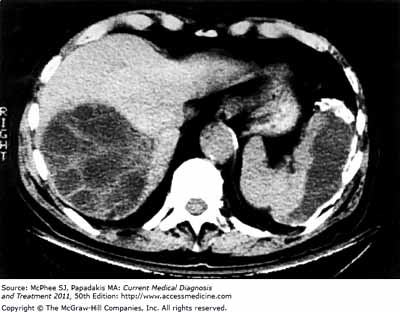

Các dấu hiệu và triệu chứng lâm sàngNgười nhiễm loài ký sinh trùng E. granulosus dẫn đến sự phát triển một hoặc nhiều nang sán nằm chủ yếu ở gan và phổi, và thỉnh thoảng nằm trong xương, thận, lá lách, cơ, hệ thống thầnkinh trung ương và mắt.

Siêu âm là kỹ thuật hình ảnh được lựa chọn cho việc chẩn đoán cả hai hình thức đó là bệnh nang sán Echinococcosis và bệnh ở phế nang hay phổi. Kỹ thuật này thường được bổ sung hoặc xác nhận bởi chụp cắt lớp vi tính (CT-scanner) và/ hoặc chụp hình cộng hưởng từ (Magnetic Resonance Imaging_MRI).

Đôi khi, các u nang có thể phát hiện tình cờ bởi chụp x-quang. Kháng thể đặc hiệu được phát hiện bằng xét nghiệm huyết thanh khác nhau và có thể hỗ trợ chẩn đoán. Sinh thiết và hướng dẫn siêu âm cũng có thể được thực hiện đối với chẩn đoán phân biệt u nang từ các khối u và áp-xe.